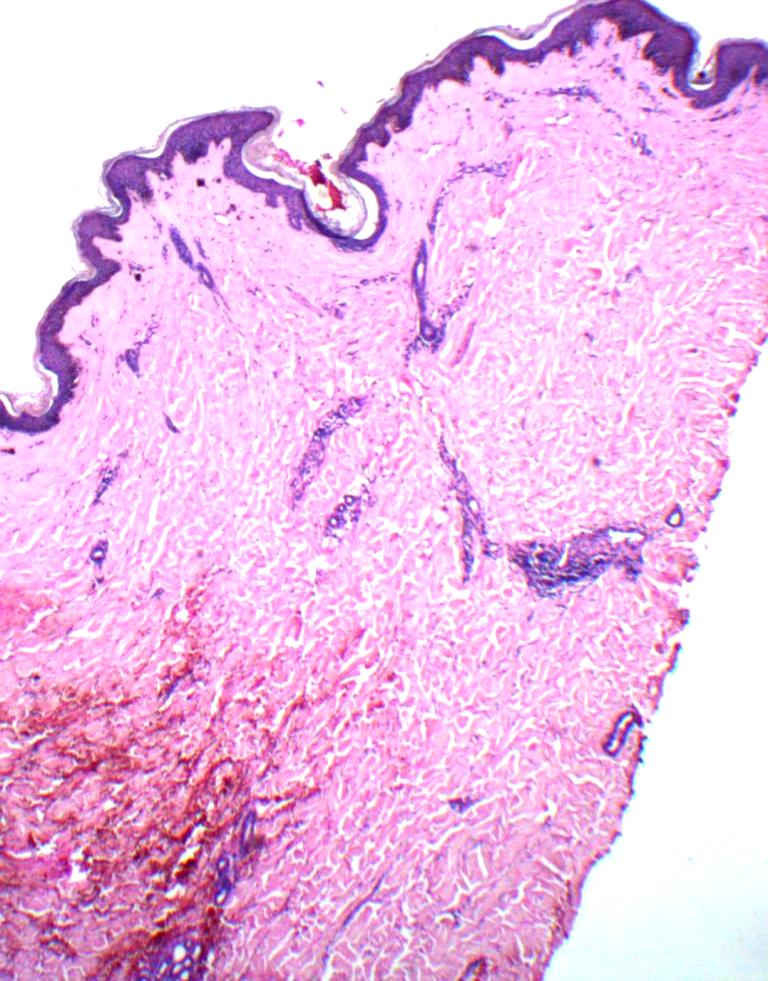

Fig 3: Skin biopsy from thigh lesion showing atrophic epidermis, vacuolar interface and hylinized papillary dermis. (H&E, 40X)